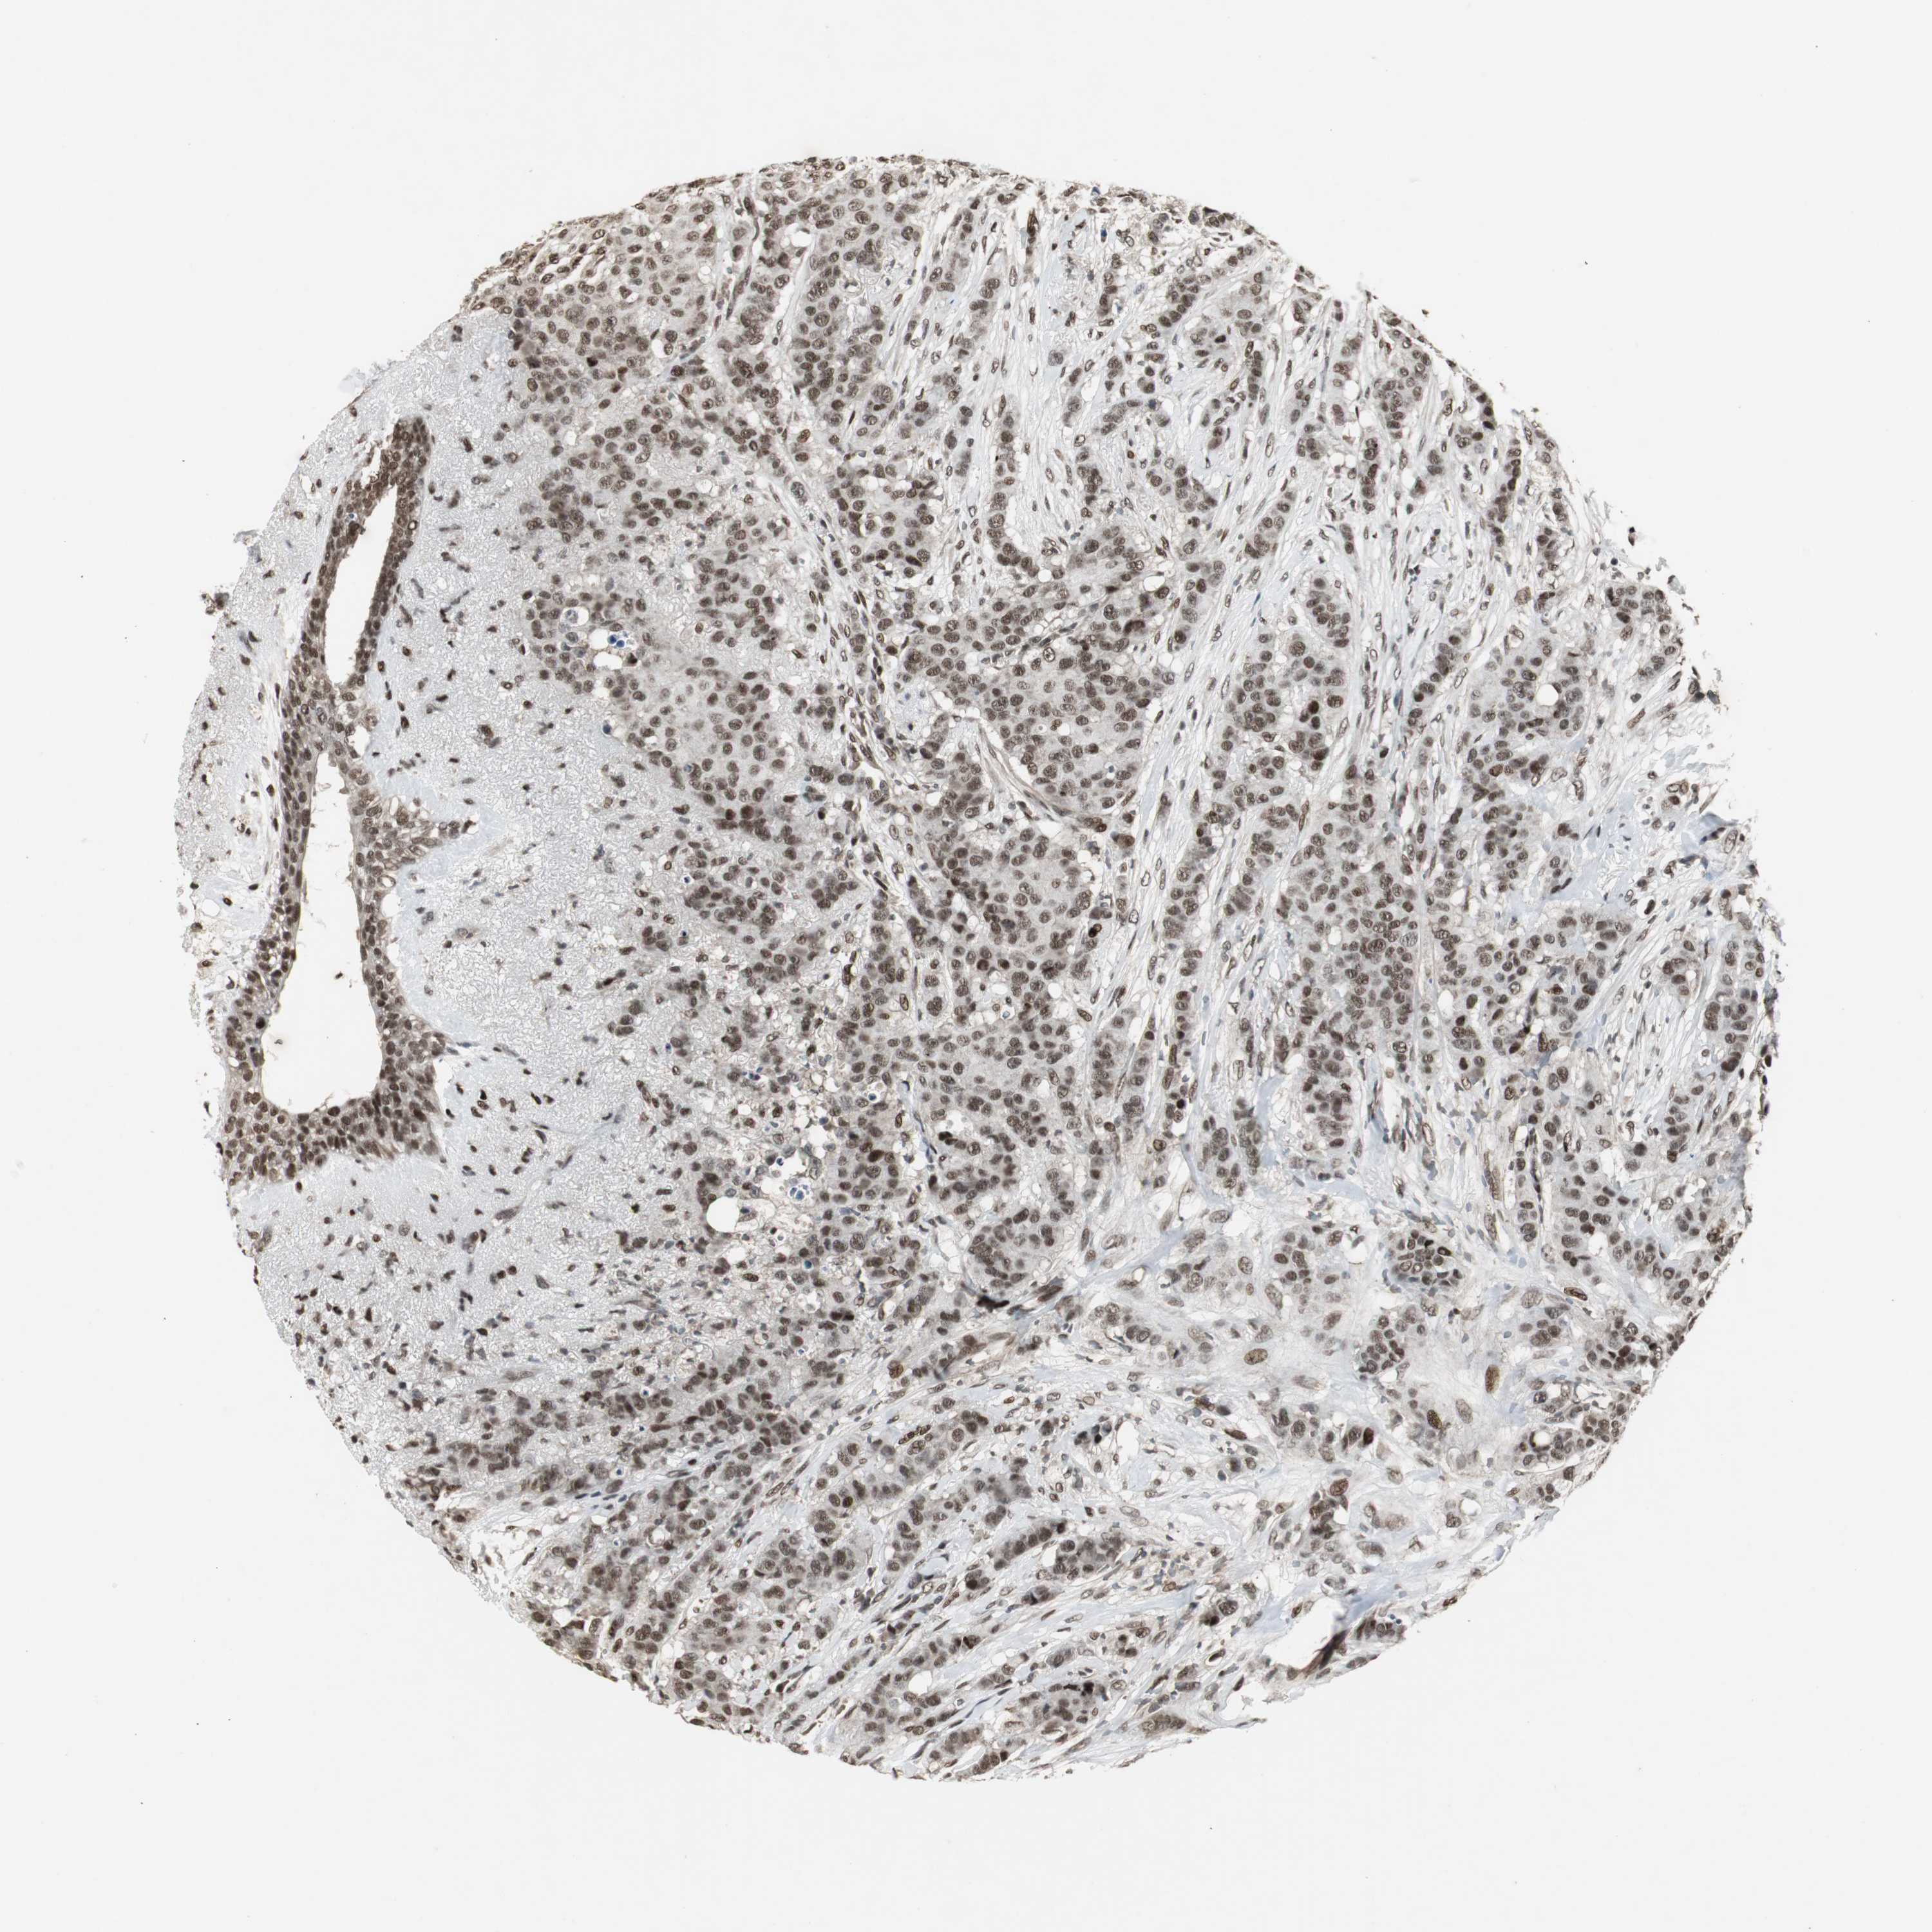

BRCA TCGA BRCA VALIDATION PROTEIN EXPRESSION

ANTIBODIES

AND

VALIDATION